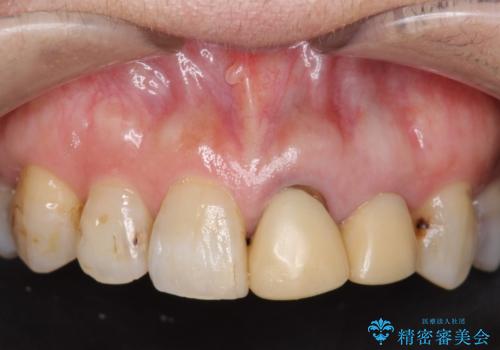

左上2抜歯後、骨および歯肉の回復を待ち、オールセラミッククラウンのブリッジによる欠損補綴を行いました。